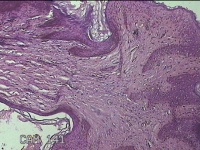

左侧会阴部皮下结节

性别

女

年龄

45岁

临床诊断

皮下结节

一般病史

发现左侧会阴部皮下结节2年余,伴近日局部隐痛不适。

标本名称

大体所见

灰白暗红色结节0.8x0.7x0.3cm一个,表面糜烂。

图4